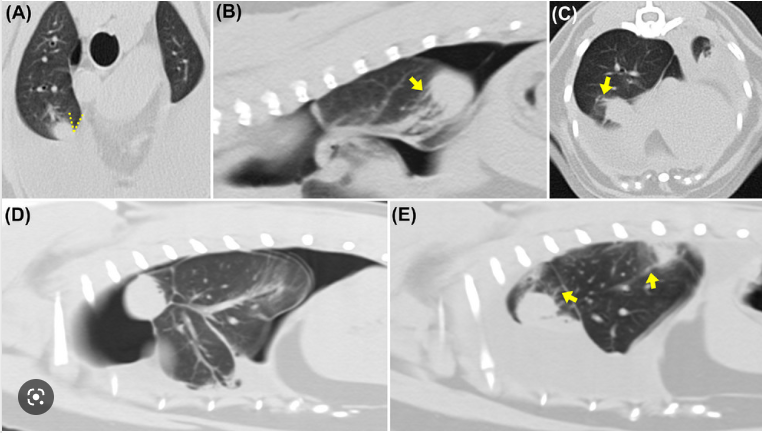

이번 소개할 논문은 CT상에서 만성염증에 의한 둥근 무기폐(rounded atelectasis) 양상이다.

이런식으로 폐 내에 결절성으로 병변이 관찰되어 원발성 폐종양을 의심하게 하지만

혈류 신호와 주변 폐혈관, 기관과의 관계성을 고려할 때 종양으로 보기 어려운 상황이 있기 때문에 알아둬야 한다.

농흉이 만성적으로 발생하는 경우 잘 발생하는것으로 알려져 있다.